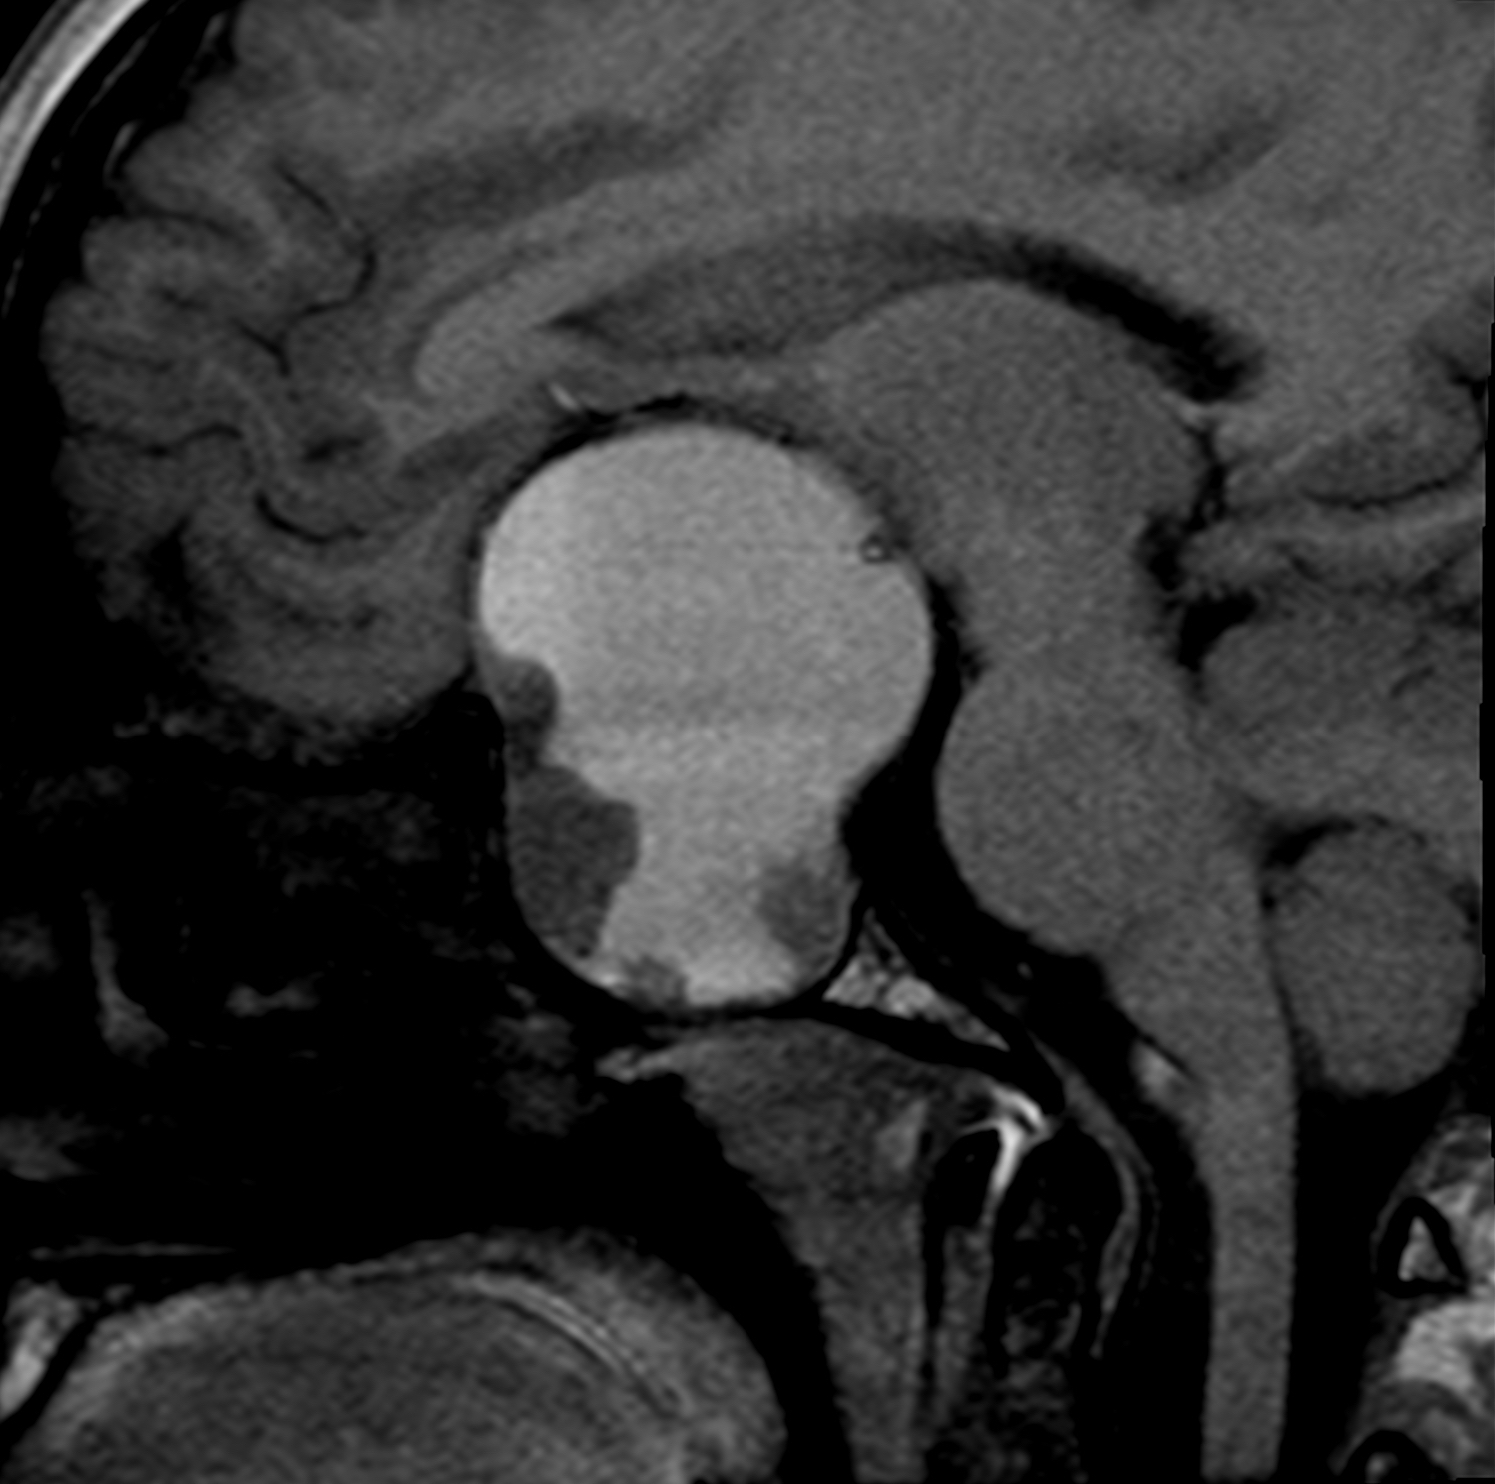

MRI results revealed a 5.5-cm solid and cystic mass with multiple fluid levels in the sellar and suprasellar areas, displacing and compressing the optic nerves and optic chiasm (Figures 1-3).

Figure 1. Sagittal precontrast T1-weighted image showing a 5.5-cm cystic and solid mass expanding into the sella. The fluid level in the hyperintense cystic component suggests internal hemorrhage.